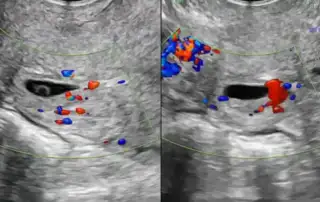

Pepper Training model for hysteroscopy ans sonographic image of adeno-myosis.

DOI: 10.36205/trocar6.2025016 - Effective Management of Pregnant Women with Adenomyosis A Comprehensive Approach to Minimize Adverse Pregnancy Outcomes

Effective Management of Pregnant Women with Adenomyosis: A Comprehensive Approach to Minimize Adverse Pregnancy Outcomes: a Review

DOI: 10.36205/trocar6.2025017